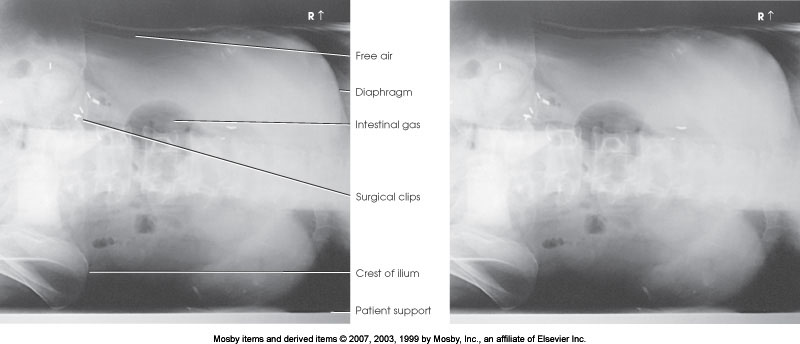

What position is demonstrated?

AP Upright Abdomen